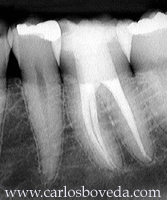

Video de un Tratamiento de Conductos en Una Sesión - (formato Quicktime)